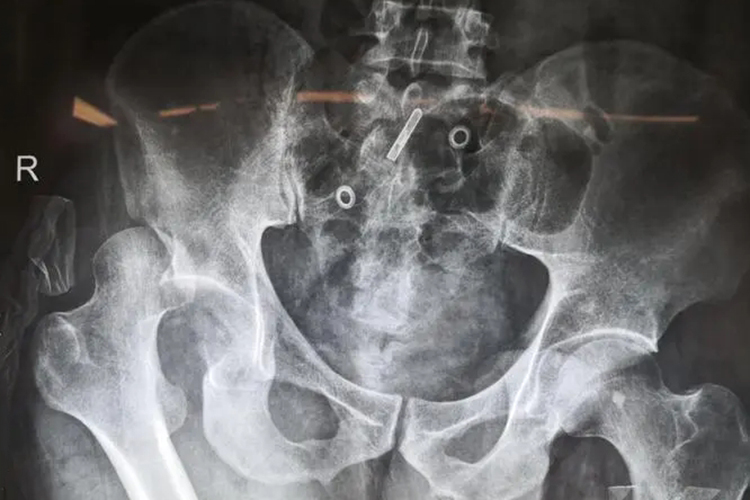

出现髋关节脱位时应及时就医,在医生操作下进行手法复位、牵拉复位。若复位失败,或合并髋臼骨折、骨折块较大者,应早期手术切开复位内固定。骨折块可用螺钉或钢板固定。